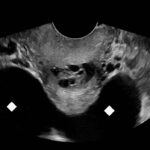

Ovarian hyperstimulation syndrome (OHSS) is a potentially life-threatening complication of assisted reproductive technology (ART). Here, we present the case report of a 30-year-old female undergoing infertility treatment who presented to the emergency department (ED) with nausea and vomiting, abdominal distention, and shortness of breath. On physical exam, she had notable ascites. Computed tomography (CT) of the abdomen and pelvis and pelvic ultrasound (US) revealed significant ascites and enlarged ovaries with multiple cysts. She was diagnosed with severe OHSS and admitted to obstetrics and gynecology (OBGYN) service for five days where she underwent intravenous (IV) hydration and paracentesis. This case report reviews the clinical presentation, categorization, management, and prevention of OHSS and provides examples of imaging findings consistent with the condition.